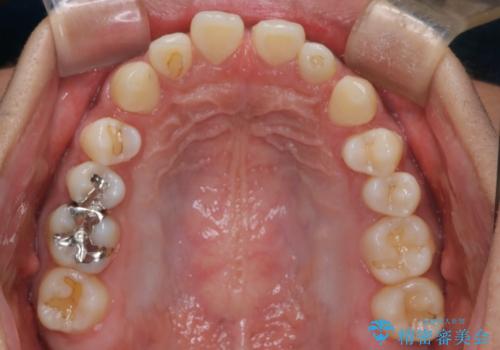

【インビザライン】空隙歯列の矯正

- 前歯の隙間を主訴に来院されました。

なるべく目立たない治療を希望されましたので、インビザラインにて治療を行なっております。

単純に前歯の隙間の閉鎖をしてしまうと、前歯に早期接触が生まれ、臼歯が噛まなくなってしまいます。適切な治療計画を立てることで、噛み合わせも良好な結果を得ることができました。